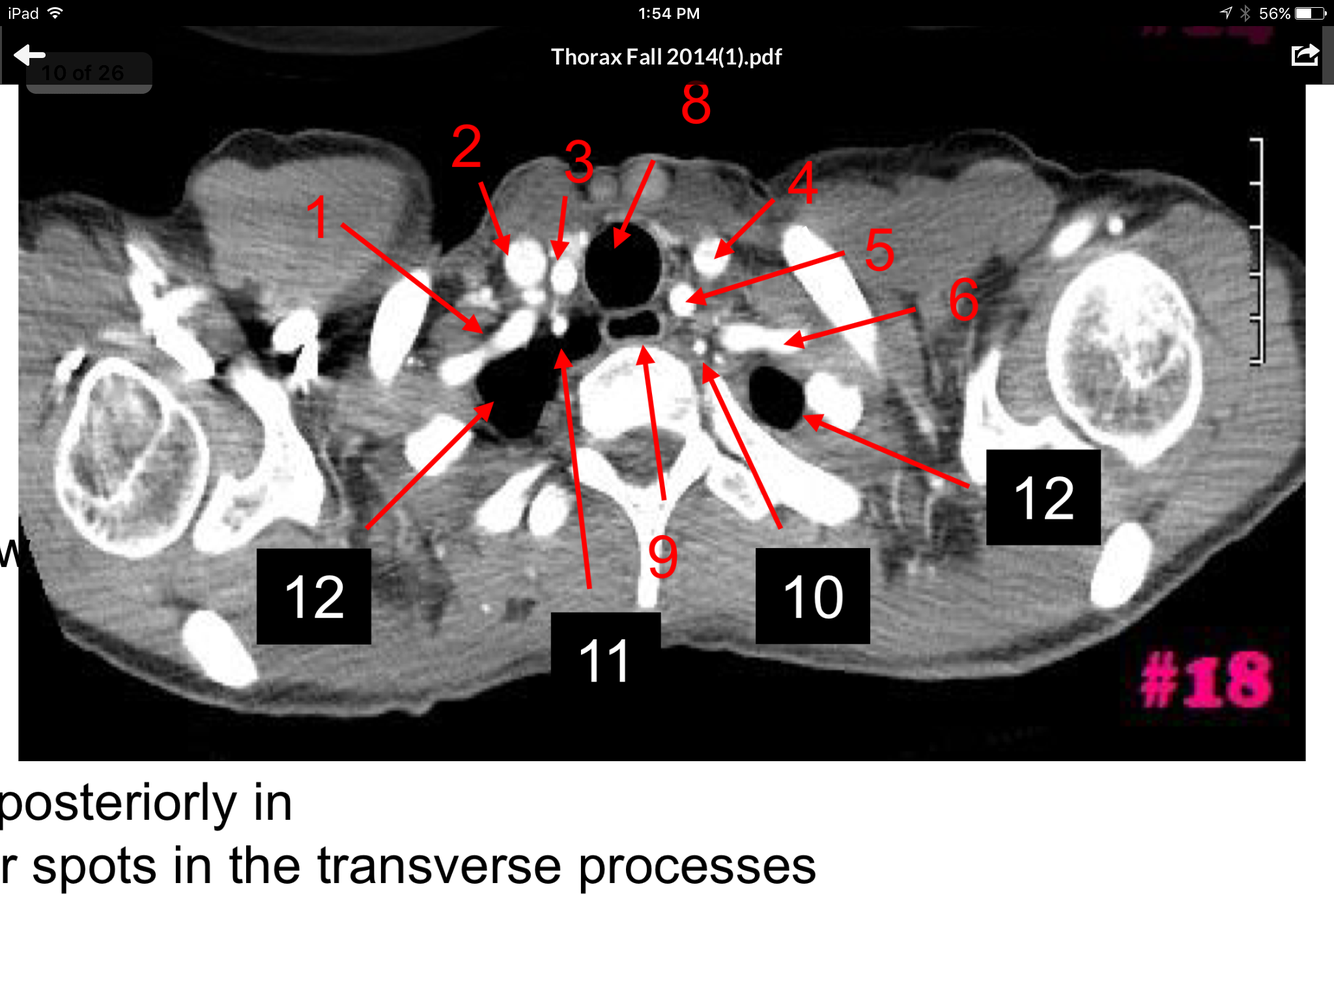

3

Q

A

Rt brachiocephalic vein

Lt brachiocephalic vein

Brachiocephalic artery

Lt common carotid artery

Manubrium of the sternum

Lt subclavian artery

Esophagus

How well did you know this?